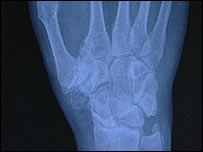

手部的X光照片

伦凯伊手部的X光照片

伦凯伊在英格兰南部海滨小镇沃辛(Worthing)的医院的手术是从他的右手腕部切除了部分骨头,并融合了几个关节,以求缓解关节炎病状。